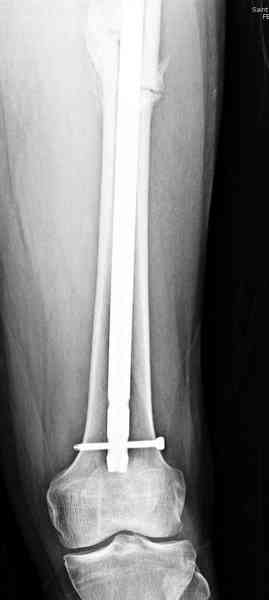

Здесь представлены снимки больного 65 лет, поступившего с диагнозом перелом

бедра после автоаварии.

В первый же день произведено антеградное штифтованием DePuy Trochanteric Nail.

На второй день (7) обнаружен пропущенный перелом,

сделаны Компьютерная Томограмма

и проведены шурурпы через и спереди штифта без удаления.

Послеоперационные снимки